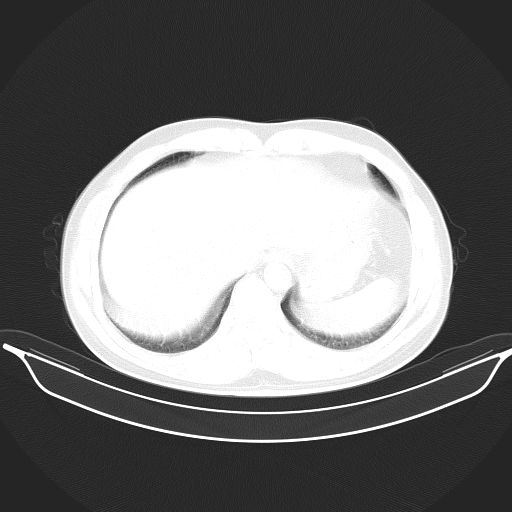

标题: CT25490:男,40岁,体检发现;无其它不适。 [打印本页]

标题: CT25490:男,40岁,体检发现;无其它不适。

考虑:1、过各敏性肺炎可能性大,建议定期复查。

2、轻度脂肪肝。

3、建议查血。